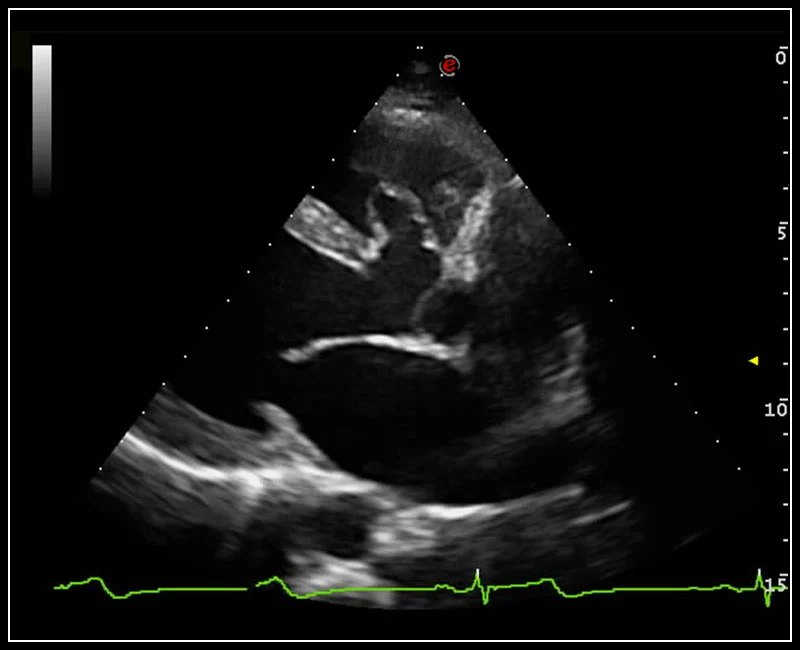

MyLab™C30 - Bmode - Plax

MyLab™C30 - Bmode - Plax

MyLab™C30 - Bmode - 3CH

MyLab™C30 - Bmode - 3CH